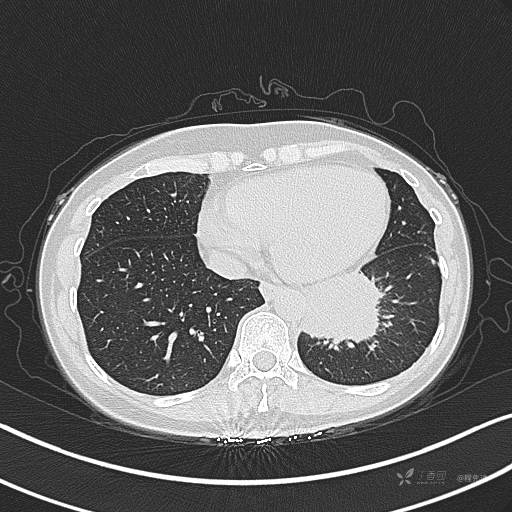

CT平扫

肺窗